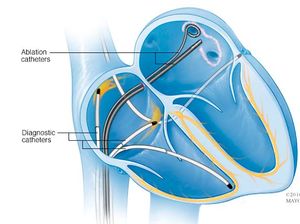

سيقوم الطبيب بإدخال القسطرة عبر الجراب وتوجيهه إلى العديد من الأماكن داخل القلب. ربما يقوم الطبيب بحقن صبغة في القسطرة، الأمر الذي يساعد فريق الرعاية في رؤية الأوعية الدموية والقلب باستخدام التصوير بالأشعة السينية. تحتوي القسطرة على أقطاب على الأطراف يمكن استخدامها لإرسال نبضات كهربائية إلى قلبك وتسجيل النشاط الكهربي لقلبك.

هذا الإجراء الذي يستخدم التصوير والاختبارات الأخرى لتحديد ما يسبب اضطراب نظم القلب يسمى دراسة الفيسيولوجيا الكهربية (EP). عادةً ما يتم إجراء دراسة الفيسيولوجيا الكهربية قبل الاستئصال القلبي لتحديد الطريقة الأكثر فعالية لعلاج اضطراب نظم القلب.

بمجرد تحديد نسيج القلب الشاذ الذي يسبب اضطراب النظم، سيقوم الطبيب بتوجيه أطراف القسطرة إلى مكان نسيج القلب الشاذ. ستنتقل الطاقة عبر أطراف القسطرة لعمل ندب أو تدمير النسيج الذي يسبب اضطراب نظم القلب.